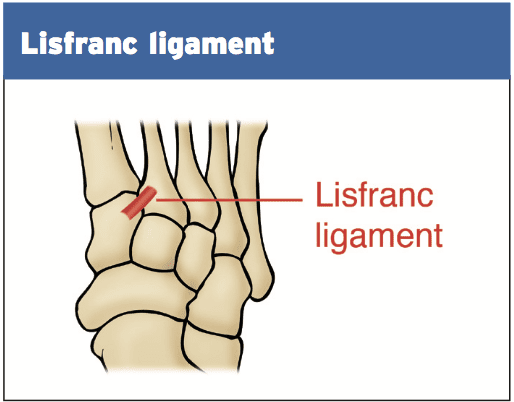

Анатомия суставов Шапарова и Лисфранка: фото и информация